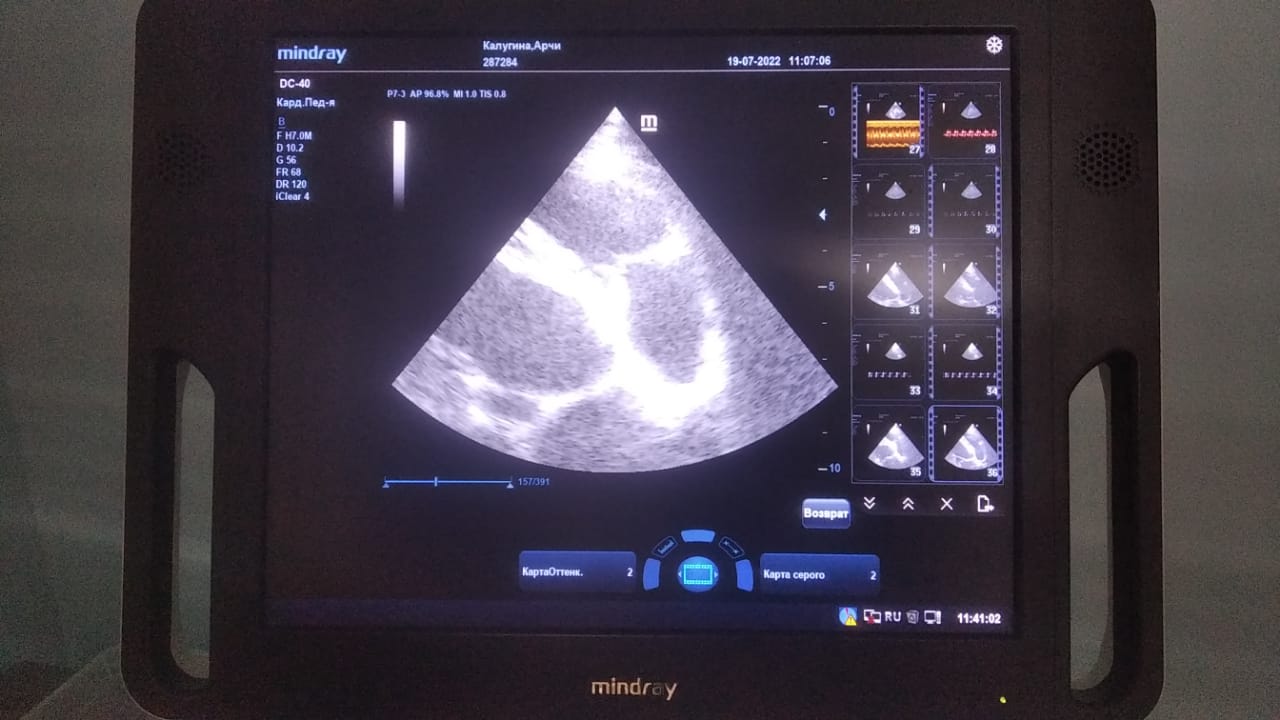

Анализы Арчи. Сердца и легких

Вложения

IMG-20220719-WA0100.jpg

IMG-20220719-WA0102.jpg

IMG-20220719-WA0104.jpg

IMG-20220719-WA0103.jpg

IMG-20220719-WA0105.jpg